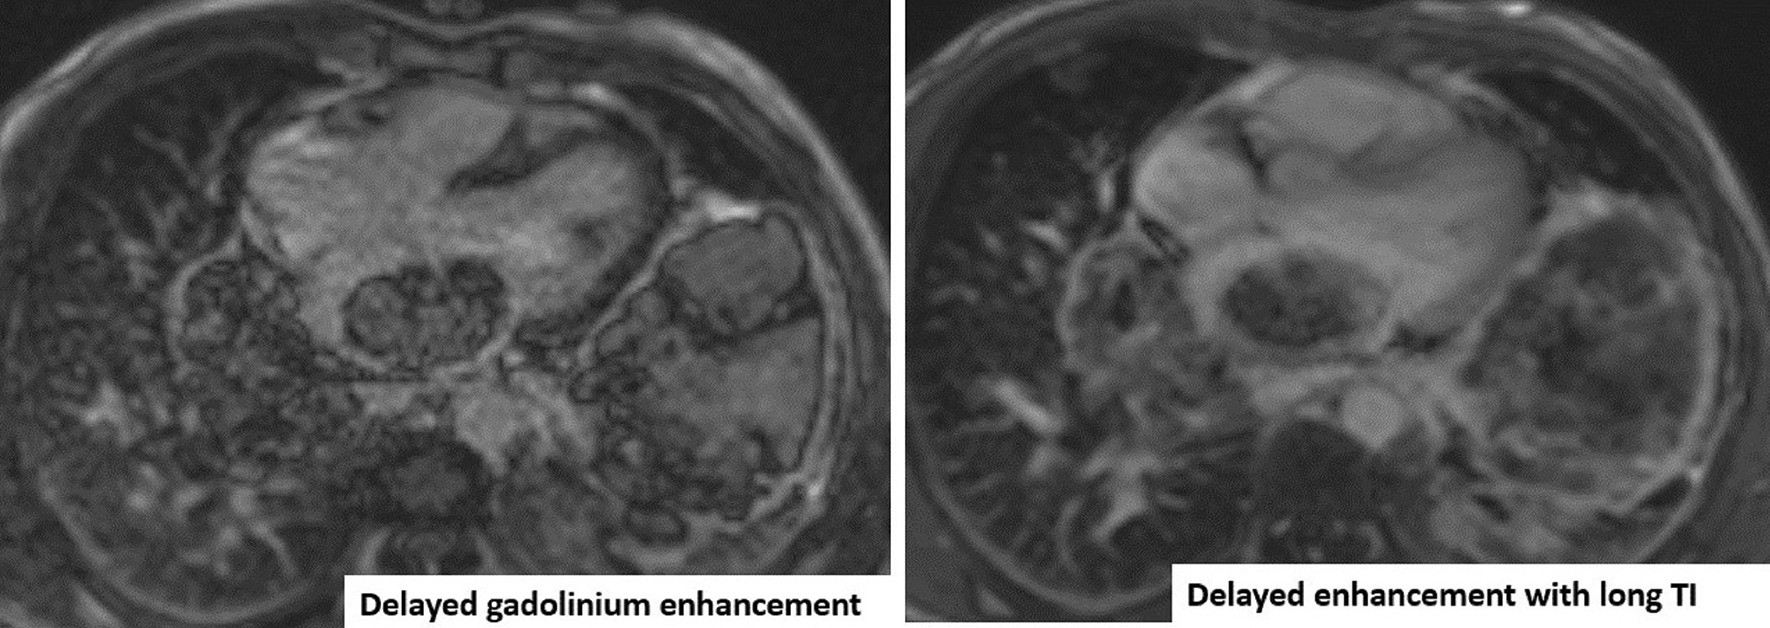

Case 4. LGE with myocardial nulling and long inversion time. In comparison to the long TI image, there is still enhancement in the mass with no jet-black signal seen in the long TI image